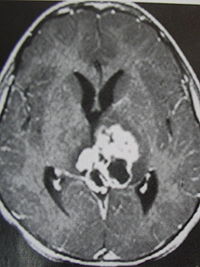

1.CT表现:

①肿瘤最常见于松果体区,位于鞍上区肿块常累及漏斗;

②CT平扫多呈等密度或稍高密度肿块,无出血、坏死及囊性变,可分叶,但境界清楚;瘤体本身钙化少见,典型松果体区生殖细胞瘤常见肿瘤包埋松果体钙化灶。

③增强扫描呈中等至明显的均匀强化。

④室管膜下转移可表现为沿脑室壁线状或条片状强化,沿脑脊液向蛛网膜下腔播散表现为脑表面、脑池的线状或结节状强化。

2.MR表现:

①最常见于松果体区,也常见于鞍上,可同时或单独存在。

②T1加权为略低信号或等信号,T2加权常呈等信号或高信号。

③增强后;呈明显均匀一致强化,并能发现沿脑脊液或室管膜转移的病灶。